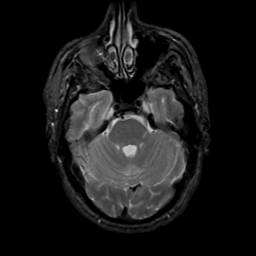

MR Study #6, March 17, 1991 -- Slice #14

[Home][Help][Clinical][Tour 1][Tour 2] Slice 14